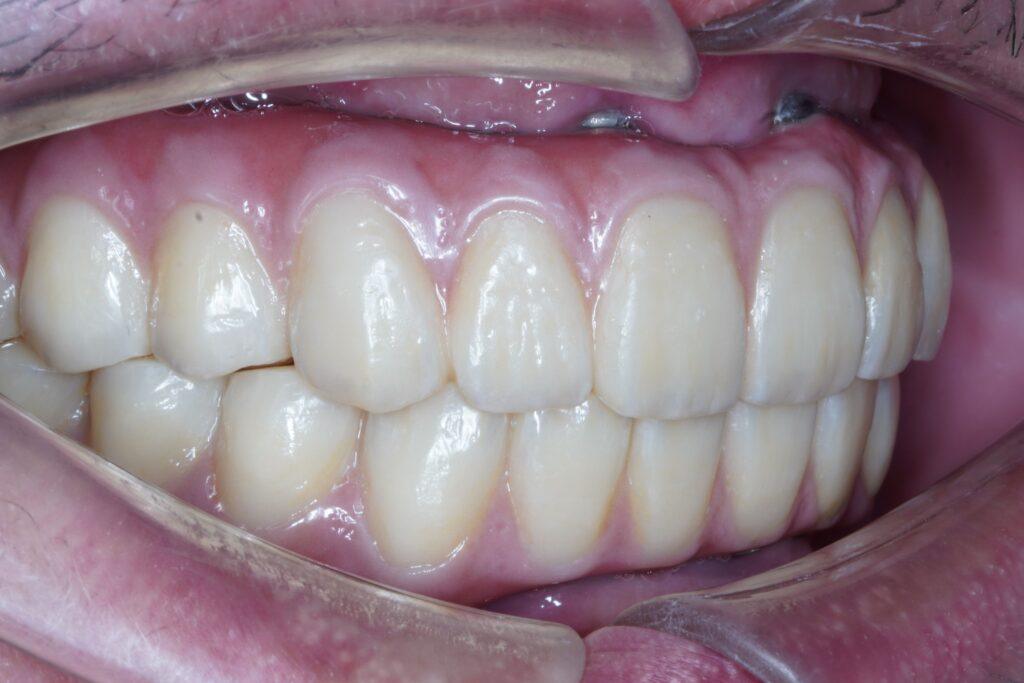

- 3~6個月後安裝最終全瓷牙橋

林楚喬醫師All on 6成功案例

至今,我已幫助超過百位中重度缺牙者完成全口重建,有的是老師、有的是企業主、有的是長年忍耐活動假牙的長輩。他們的笑容,就是我最大的成就。